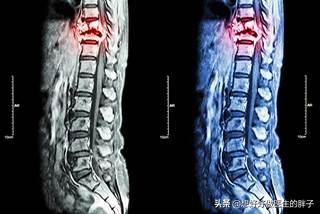

骨転移の磁気共鳴画像法

胸椎に発生した骨転移性癌を示す。

がんによる骨転移患者の痛みには一定の特徴がありますが、一般的な病気と干渉する症状も見受けられます。もし患者が発生した場合、脊椎の骨転移が神経を刺激し、医師や患者が椎間板ヘルニアによって誘発された症状を誤診しやすく、この時、患者として、体に異常があるため、適時に医師の助けを求め、医師として患者とコミュニケーションを図り、比較的質の高い検査を行い、骨転移のリスクを除外しようとする。例えば、高齢者の長期的な腰痛に対しては、レントゲン検査の代わりにMRI検査を行うことをよく勧める。例えば、慢性的な腰痛を持つ高齢者に対しては、レントゲン検査の代わりにMRI(磁気共鳴画像装置)検査を受けるよう勧めることがよくあります。